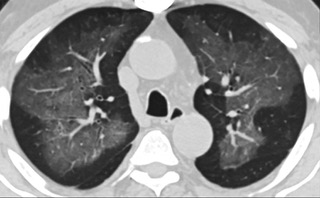

![6AYɨCTfʹ_ܤ]nt]QacT(ïfCT_)](./W020210804330783277896.jpeg)

ݐ6AYɨCTfʹ_ܤ]nt]QacT(ïfCT_)